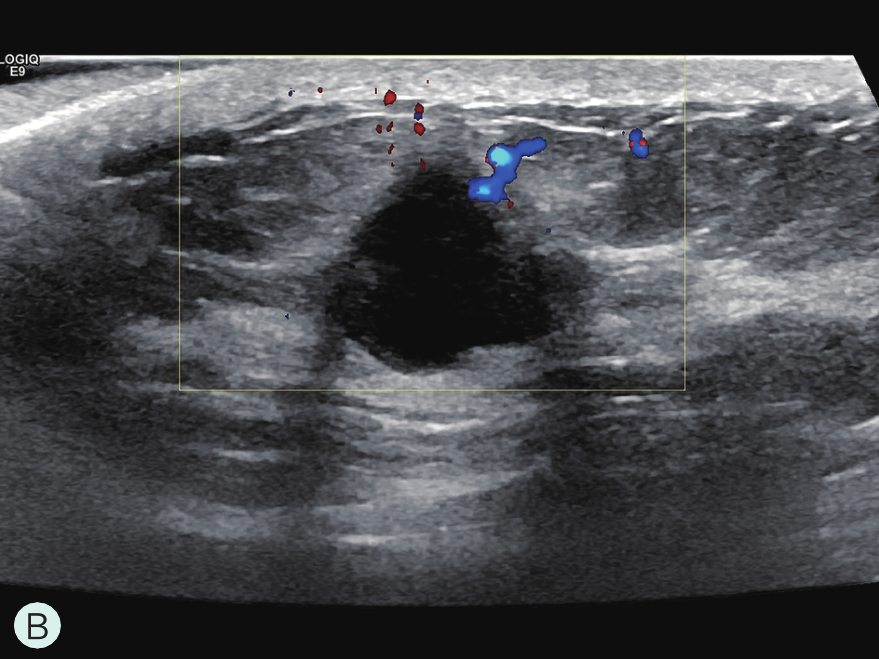

造影前应用传统灰阶超声全面扫查患侧乳腺及腋窝,重点扫查既往检查可疑病灶所在象限,结合既往检查确定超声造影靶目标及造影切面。评估病灶所在部位乳腺腺体致密性,二维及彩色多普勒(CDFI)超声常规检测肿块的大小、形态、边界、内部回声、血流及与周边组织的关系,充分利用现有超声新技术(如弹性成像)全面评估病灶。当病灶位置表浅、位于乳头后方或与探头耦合不佳时,可应用超声垫。

图2-2-1 确定造影病灶

A.病灶二维图像;B、C.病灶CDFI图像;D.同侧腋窝淋巴结情况;E.病灶弹性成像图像